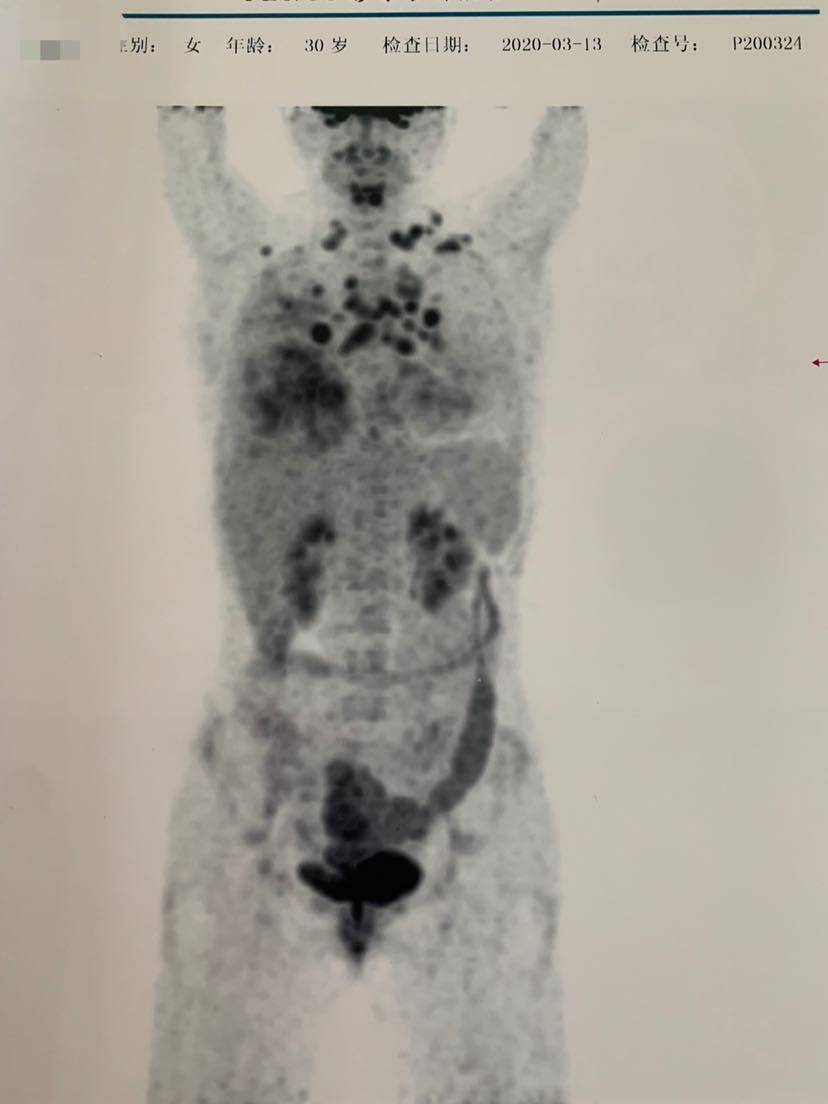

自从2020年3月确诊肺癌IV期以来,从病危到现在的CR,这次确诊15个月,入院做了个大检查,pet ct以及全套肿标,增强脑核磁,心脏彩超以及血常规等,一线阿来后,没有任何的副作用,甚至连个皮疹都没有,但是阿来的对我的效果却是极好的。确诊后每两个月一次胸部平扫➕腹部b超,一个月一次肝肾功能(10个月后由于每次都正常,后面自己也偷懒2个月一次),肿标吃药第一个月查过一次cea后面就再也没有跟随的去看过,体感一直是好的,下面附一次本次的检查单,好转看得见,继续保持啊……

发帖不通知………😡 你果然不出意外 不负众望 众望所归的CR 这个PET只为几张纸证明一下😁